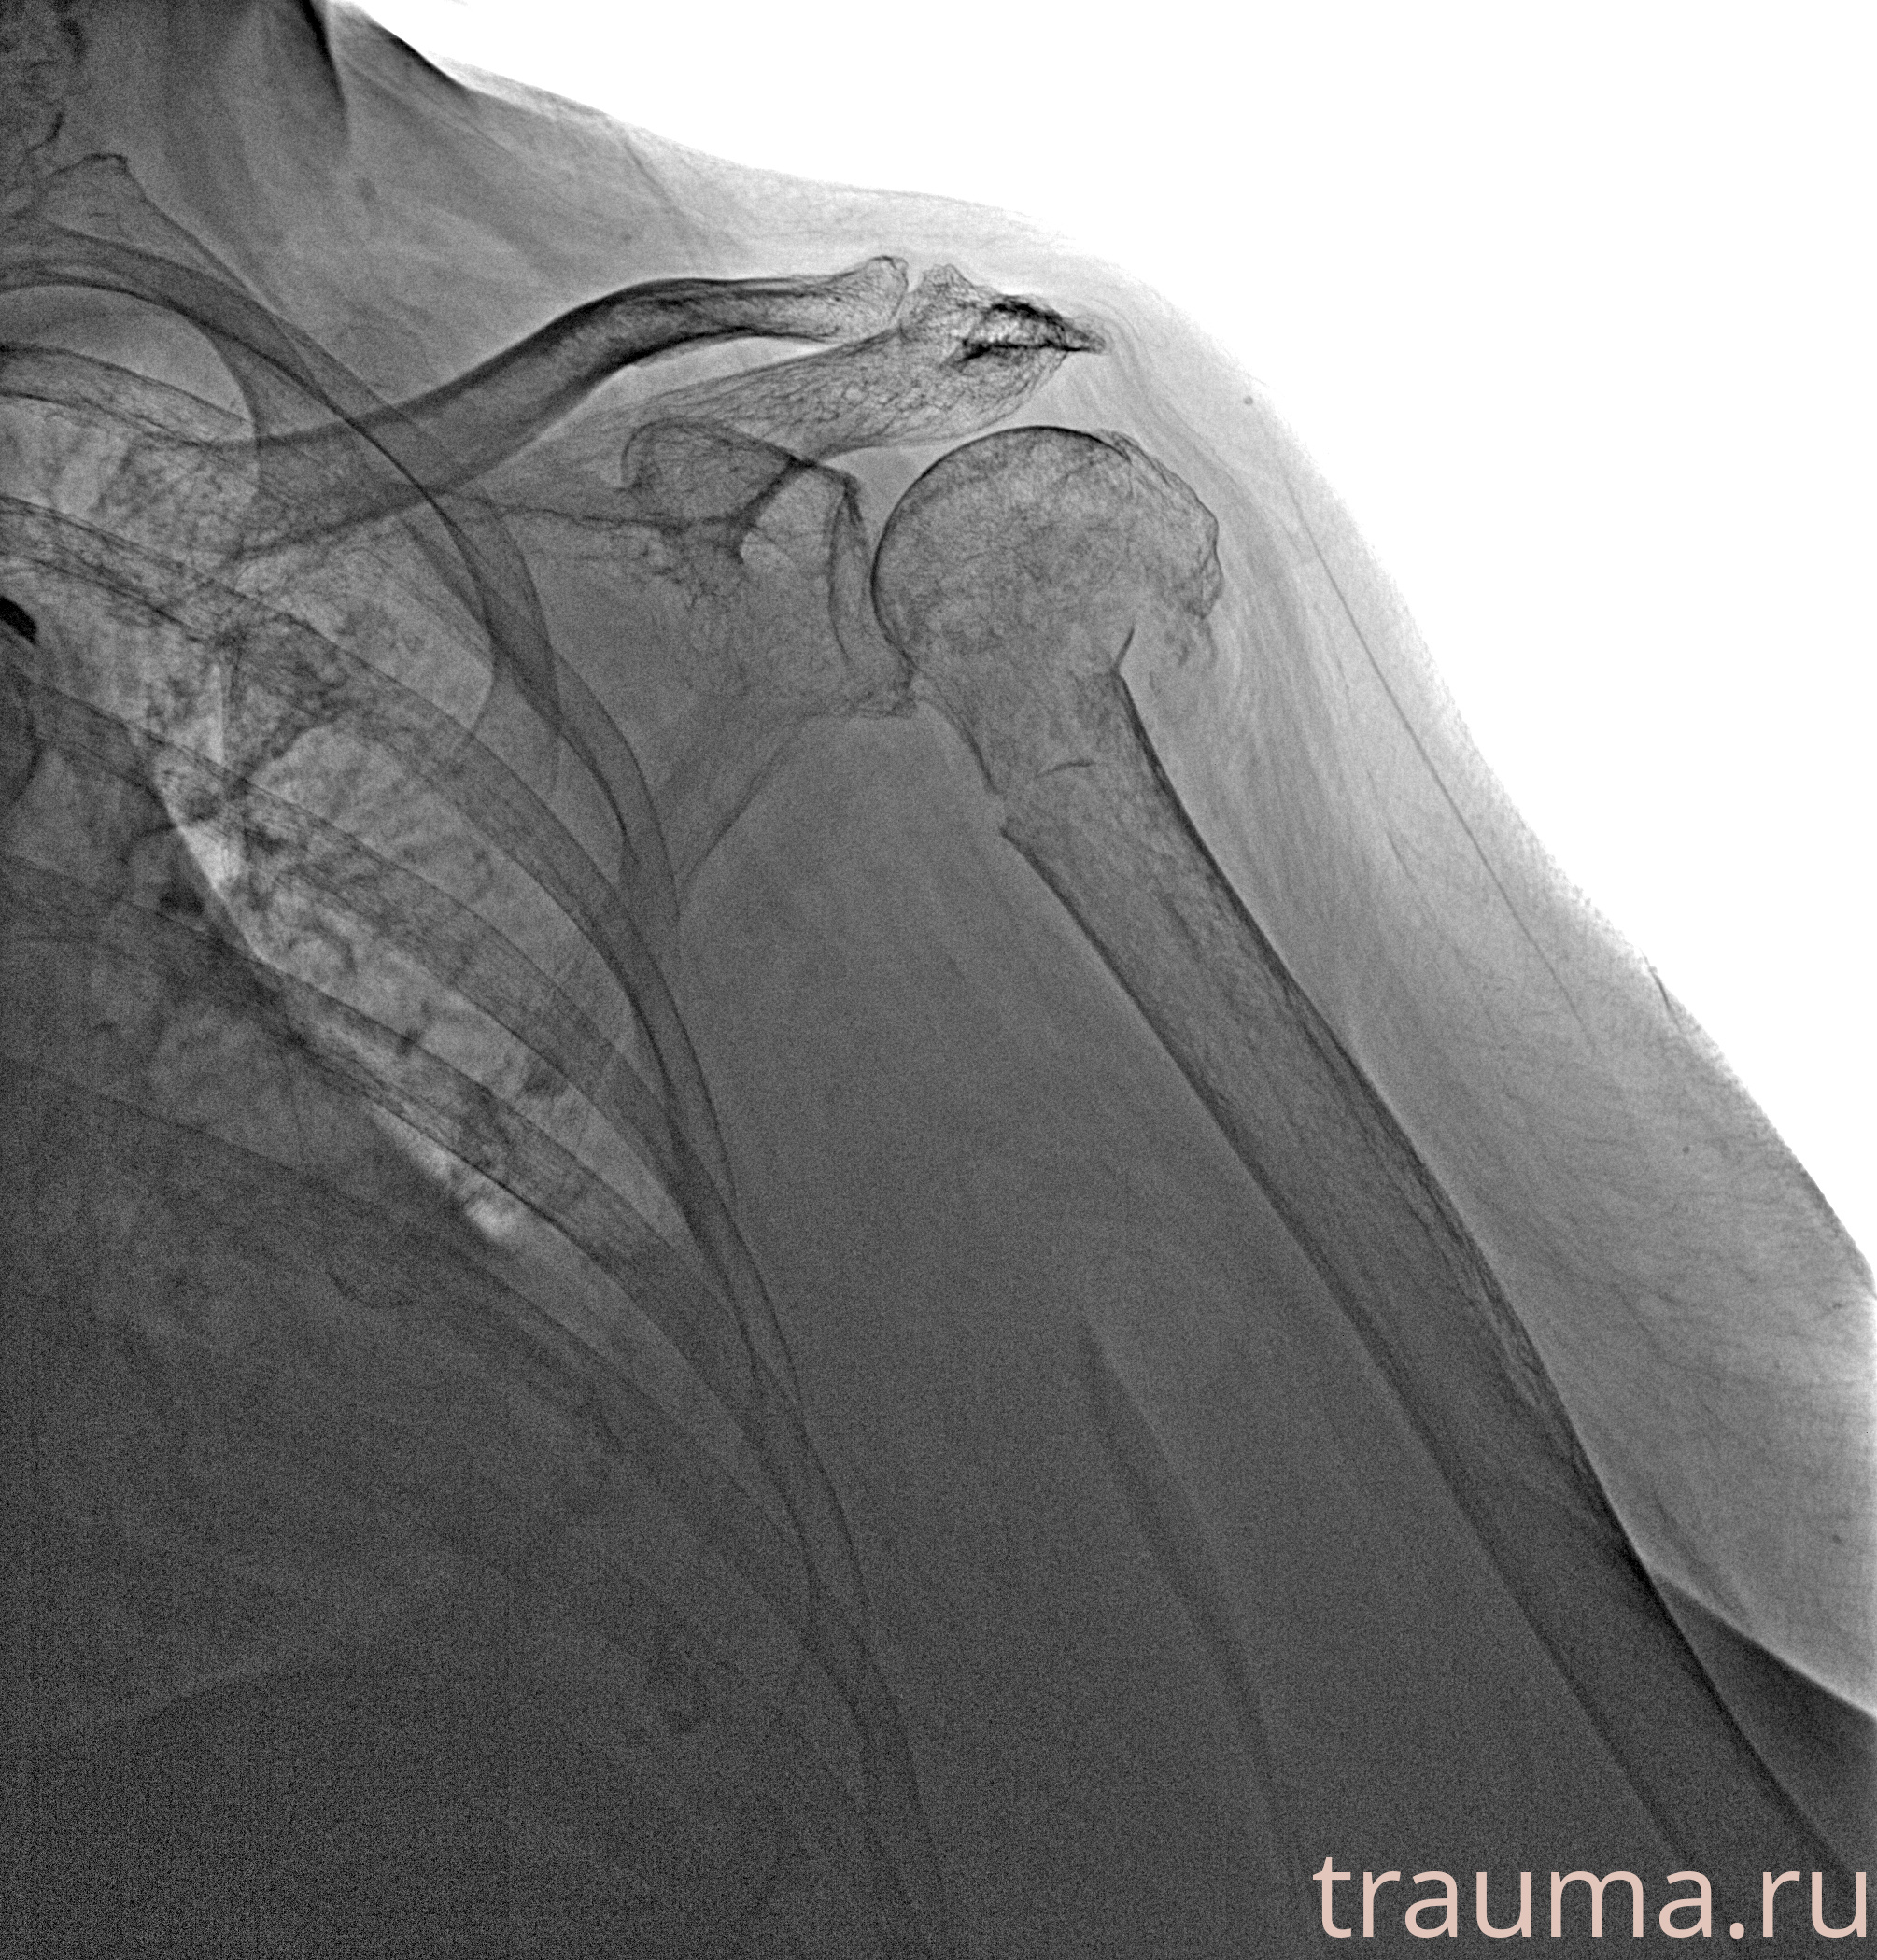

Рентгенограммы

Рентген на дому: по вашему адресу приезжает врач-рентгенолог, травматолог-ортопед с мобильным рентгеновским аппаратом, проводит диагностику травмы или заболевания, делает необходимые рентгенограммы, дает рекомендации по дальнейшему лечению. Получить качественные снимки в домашних условиях возможно благодаря уникальной методике, разработанной МосРентген Центром для института  Склифосовского